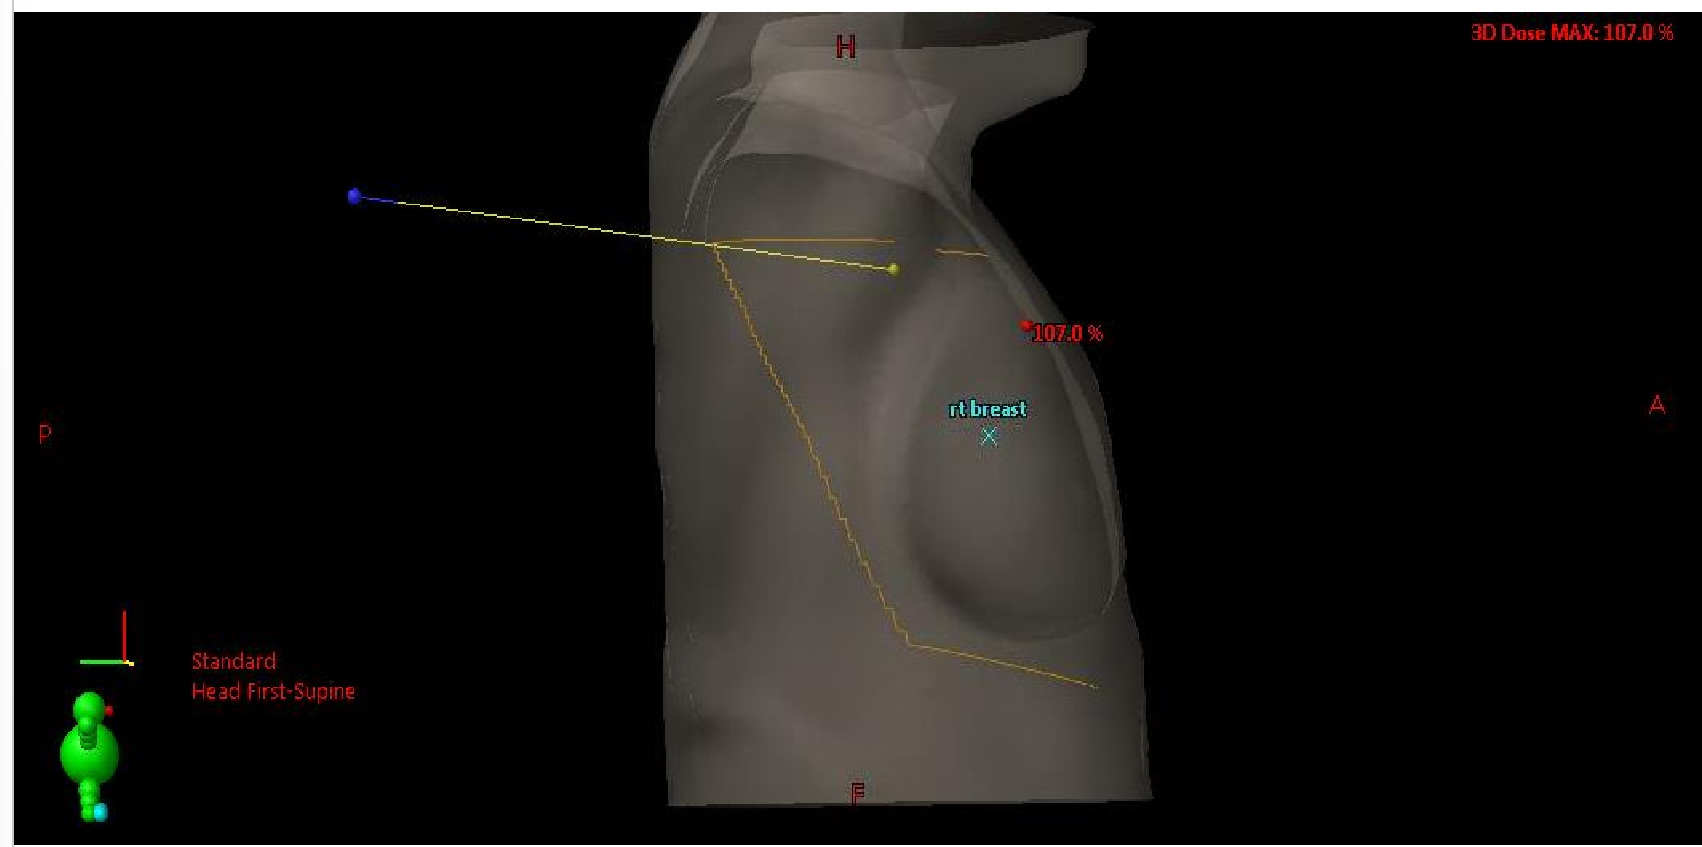

important: what 4 things are we evaluating with the BEV image assessment

MLC shielding (in relation to the patient)

lung volume

treatment field clearance (sup, inf and ant) around the breast

bolus if applicable

BEVs are not used for field localization, but they are used to verify / confirm …

verify and confirm position of the treatment beam

what imager is used to take the BEV image

MV EPID imager

this is done to ensure field borders and MLC are within the image